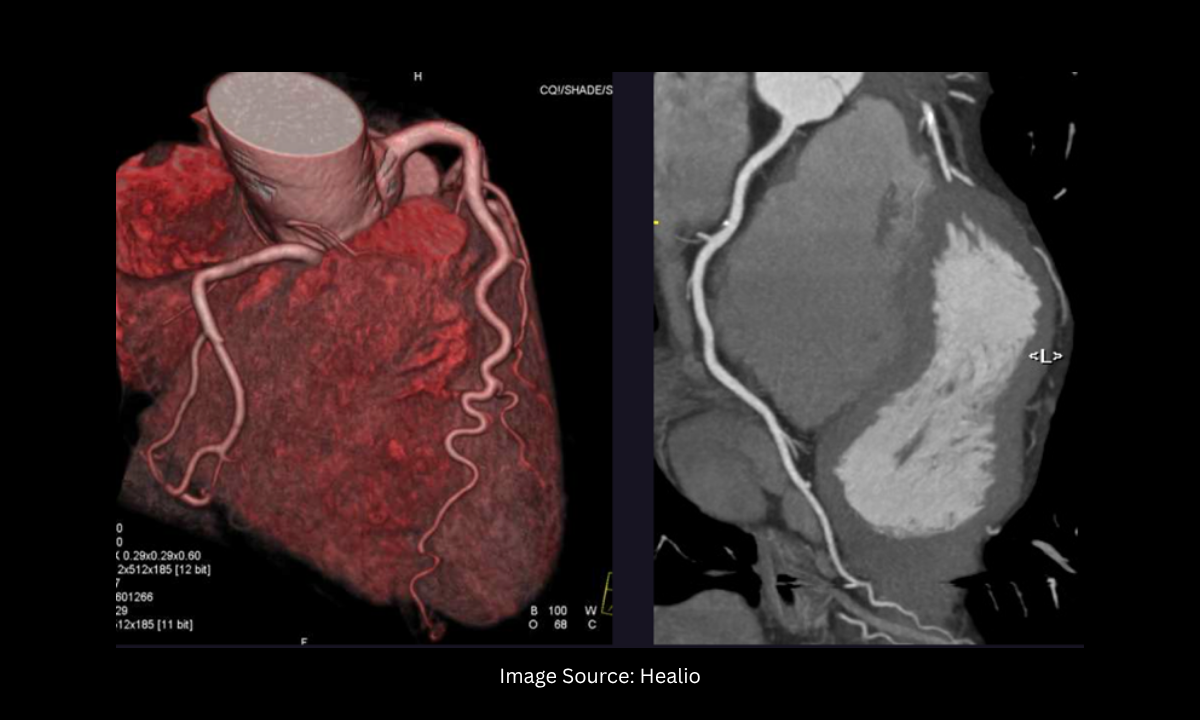

During this advanced scan, a specialized contrast dye is injected through a simple intravenous (IV) line in your arm. As this dye safely travels into your chest and illuminates your blood vessels, our state-of-the-art CT scanner rapidly captures thousands of high-resolution X-ray images in mere seconds.

A powerful computer then compiles these cross-sectional images to construct a remarkably detailed, three-dimensional model of your beating heart and its entire plumbing network.

The Clinical Advantage of 3D Visualization

The clarity provided by modern CT technology is truly revolutionary. Our specialists at Koshikaa can virtually navigate through your arteries on a computer monitor to pinpoint the exact location, density, and severity of any calcified plaque buildup. This test offers several distinct advantages over traditional surgical methods: